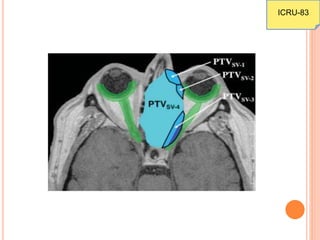

PLANNING TARGET VOLUME

 Definition same as before

 Compromising the PTV if it overlapped the OAR is

no longer recommended as in the previous ICRU

reports

 In such a situations, the PTV is subdivided into as

subvolumes.

ICRU-83

In the case of absorbed-dose

compromise in the

overlapping region between

the PTV and the PRV,

reporting theabsorbed dose

in the sub-PTV, PTVSV-1,

(left DVH) can incorrectly

represent the absorbed

dose to the underlying CTV